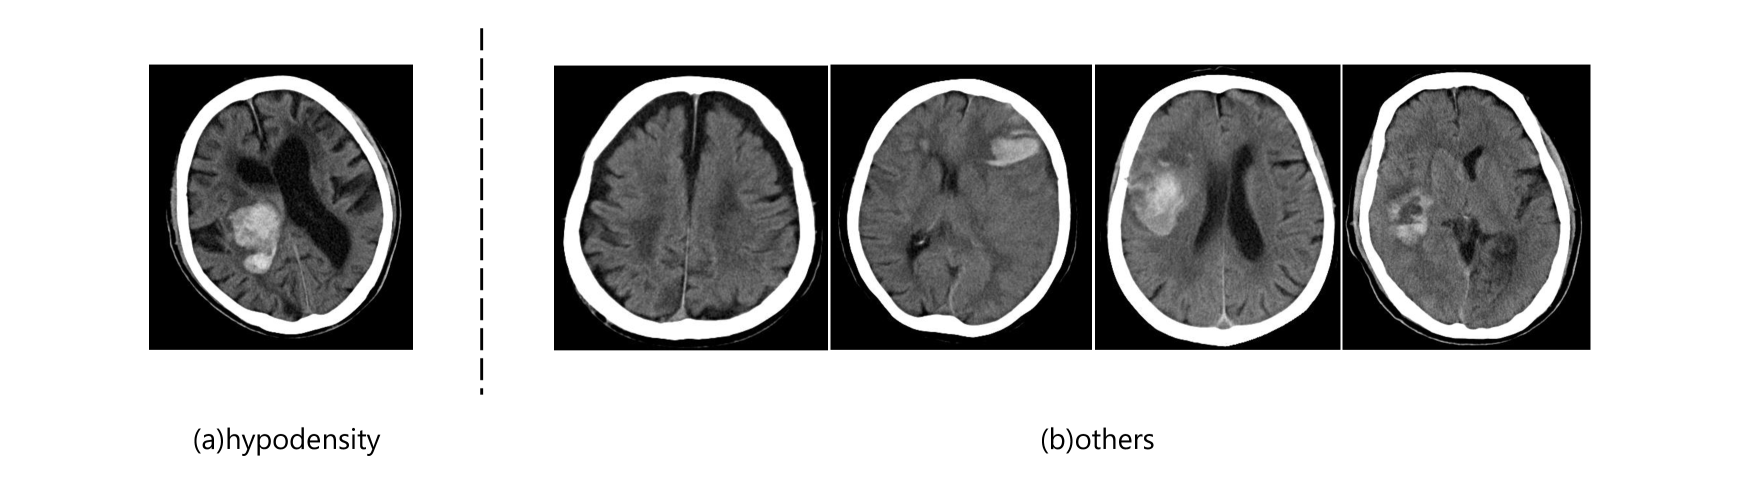

In this study, we utilize CT images, which were collected from 11 institutions. Annotation of the extent, location, and condition of hematomas on the CT scans was performed independently by specialists at each of the 11 institutions. The data is stored in DICOM format, and the pixel values are measured in Hounsfield Units (HU). The collected data is contrast-adjusted based on the HU range. Additionally, annotation data for the segmentation task exists for facilities 1 to 4. This data includes masks for pixels where hemorrhages are present. In acute intracerebral hemorrhage (ICH), markers with different names describe various appearances of hemorrhages, including hypodensity, irregular margins, blend signs, and fluid levels (refer to Figure 3). These markers, identified by different physicians as potentially useful for ICH, are discussed by Boulouis et al (2016). Consequently, the problem involves four overlapping classes, making it a multi-label task. In our experiments, we focus solely on hypodensity and frame the task as classifying whether an image exhibits hypodensity. Specifically, our dataset contains images with no hemorrhage and images that simultaneously belong to all four hemorrhage classes, but we set the task to classify only hypodensity-positive images.

Refer to caption

Figure 3: (a) Hypodensity (b) Images without hypodensity overlapping with other hemorrhage classes (from left to right: image without hemorrhage, margin irregular sign, blend sign, fluid level)